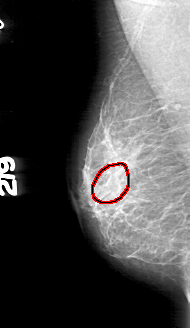

ics_version 1.0 filename D-4166-1 DATE_OF_STUDY 12 6 1997 PATIENT_AGE 44 FILM FILM_TYPE REGULAR DENSITY 2 DATE_DIGITIZED 2 6 1999 DIGITIZER HOWTEK 43.5 SEQUENCE LEFT_CC LINES 5371 PIXELS_PER_LINE 2671 BITS_PER_PIXEL 12 RESOLUTION 43.5 NON_OVERLAY LEFT_MLO LINES 5191 PIXELS_PER_LINE 2701 BITS_PER_PIXEL 12 RESOLUTION 43.5 NON_OVERLAY RIGHT_CC LINES 4786 PIXELS_PER_LINE 2416 BITS_PER_PIXEL 12 RESOLUTION 43.5 OVERLAY RIGHT_MLO LINES 4906 PIXELS_PER_LINE 2836 BITS_PER_PIXEL 12 RESOLUTION 43.5 OVERLAY |

FILE: D_4166_1.RIGHT_MLO.OVERLAY TOTAL_ABNORMALITIES 1 ABNORMALITY 1 LESION_TYPE CALCIFICATION TYPE AMORPHOUS DISTRIBUTION CLUSTERED ASSESSMENT 0 SUBTLETY 2 PATHOLOGY BENIGN TOTAL_OUTLINES 1 BOUNDARY |

FILE: D_4166_1.RIGHT_CC.OVERLAY TOTAL_ABNORMALITIES 1 ABNORMALITY 1 LESION_TYPE CALCIFICATION TYPE AMORPHOUS DISTRIBUTION CLUSTERED ASSESSMENT 0 SUBTLETY 2 PATHOLOGY BENIGN TOTAL_OUTLINES 1 BOUNDARY |